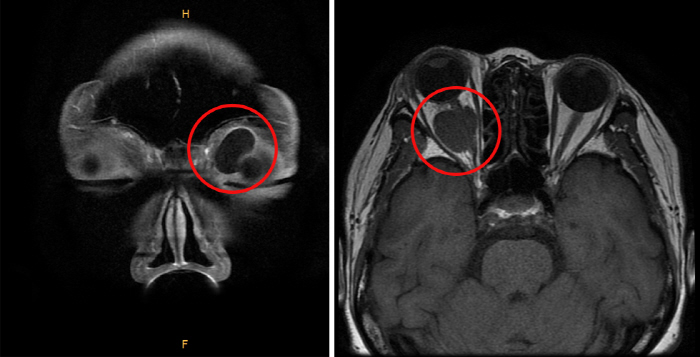

안와 양성 종양은 일반적으로 수술을 통해 제거할 수 있으나, 발생 위치에 따라 합병증 발생 위험이 있을 수 있으므로 신중하게 치료 방향을 결정해야 한다. 먼저 수술 전 CT 및 MRI 검사를 통해 종양의 크기, 위치, 성상을 정확하게 파악하고 분석한다. 안와 앞쪽에 위치한 종양은 상대적으로 쉽게 제거할 수 있다. 흉터 없이 제거하기 위해 쌍꺼풀 라인을 따라 절개하고 수술을 진행하기도 한다.

안와 뒤쪽에 위치한 종양도 종류에 따라 박리가 비교적 쉬운 종양도 있으나, 일부는 합병증 발생 위험이 있다. 특히 안구 뒤쪽으로 시신경이 뇌와 연결되는 구멍이 있는 '안와첨'은 좁은 공간 내 많은 신경과 혈관, 외안근 시작 부위 등이 가깝게 자리 잡고 있어, 종양 수술 후 합병증 발생 위험이 높아 수술 여부를 신중하게 검토해야 한다. 이에 안와첨 종양은 수술이 아닌 사이버나이프 같은 방사선치료를 통해 크기를 줄이는 치료를 시행하기도 한다.

안와 뒤쪽 공간에 종양이 발생하면, 종양의 크기가 꽤 커질 때까지 환자가 증상을 느끼지 못하는 경우가 많다. 시력이나 시야에 이상이 없고, 안구 움직임에도 영향을 주지 않는 양성종양의 경우 경과 관찰을 하는 것으로 치료 방향을 결정하기도 한다.